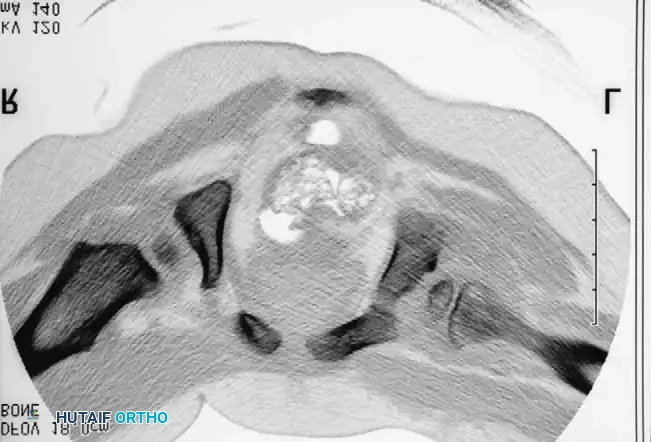

Intraoperative arthrogram demonstrating the cartilaginous contours of the femoral head and acetabulum during closed reduction.

Radiographic appearance following a complex pelvic osteotomy with internal fixation, demonstrating improved center-edge angle and acetabular coverage.